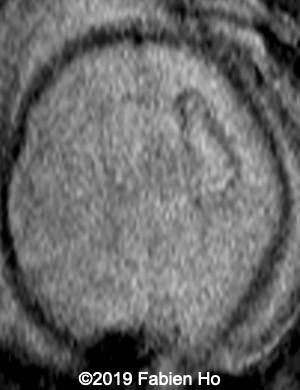

Images 12-16: we performed a second fetal brain MRI at 32 weeks, which showed the same findings as the postnatal neonatal brain MRI as follows:

The evolution of the images is typical of a clastic lesion: after resorption of the ischemic tissue and hematoma, there was now a focal porencephaly with hemosiderin tattooing on its margins. Conversely, persistence of the same MRI findings would have indicated an hypercellular brain tumor, which could have been a differential diagnosis.

12

13

14

15

16